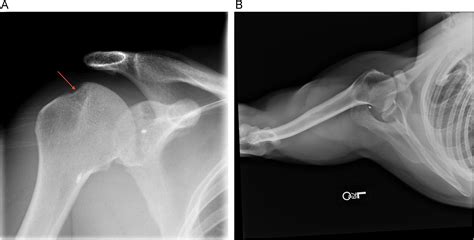

To accurately identify the extent of a Hills Sachs lesion, orthopedic specialists use various imaging techniques. A standard physical examination usually includes provocation tests to check for joint laxity, but the definitive diagnosis relies on high-quality medical imaging:

X-Ray (West Point View) Provides a specialized angle to visualize the bony defect of the humeral head.

MRI or MR Arthrogram Used to evaluate the soft tissues, specifically the labrum and surrounding ligaments.